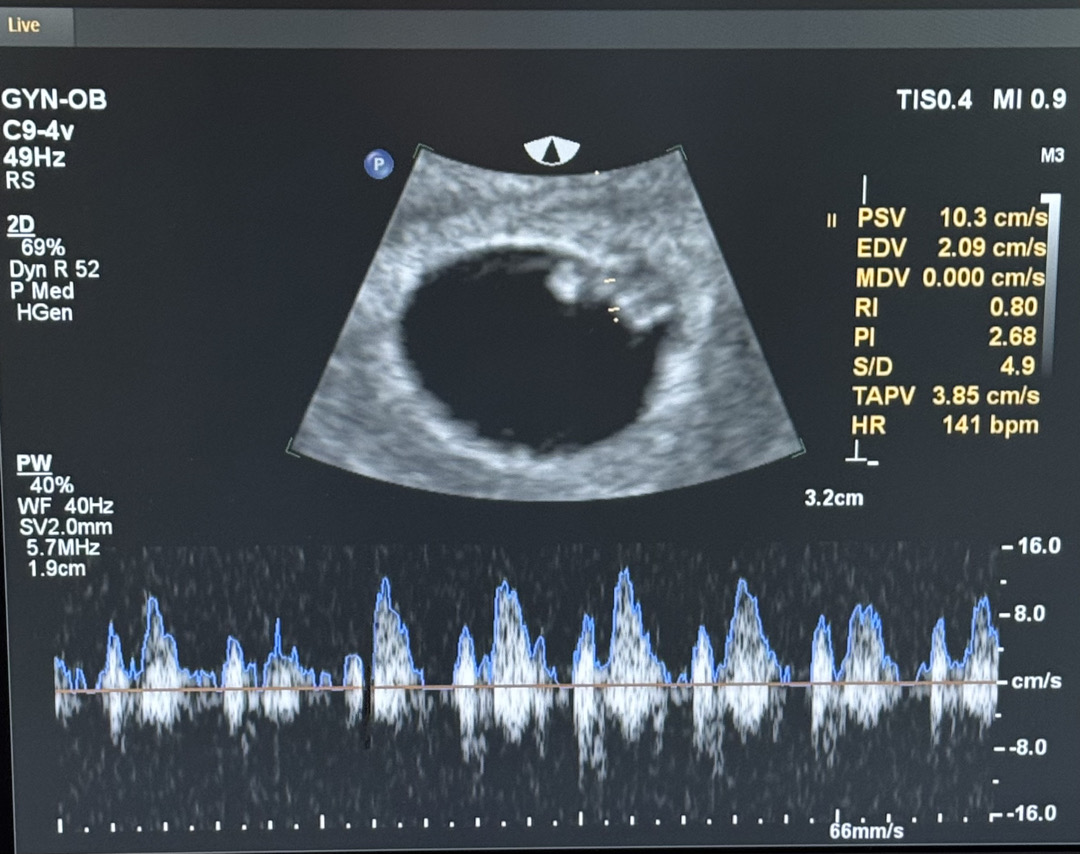

심장소리 듣고왔어요🤍

6주 3일차에 가서 심장소리 듣고왔어요! 너무 잘 있다고 말해주셔서 이제야 실감나고 안심이 되네요 ㅜㅜ 막생 7/7이라 6주 3일이였는데, 검사 후 6주 5일로 당겨졌고 4/11 출산예정일로 변경되었네요! 신기해요~😀